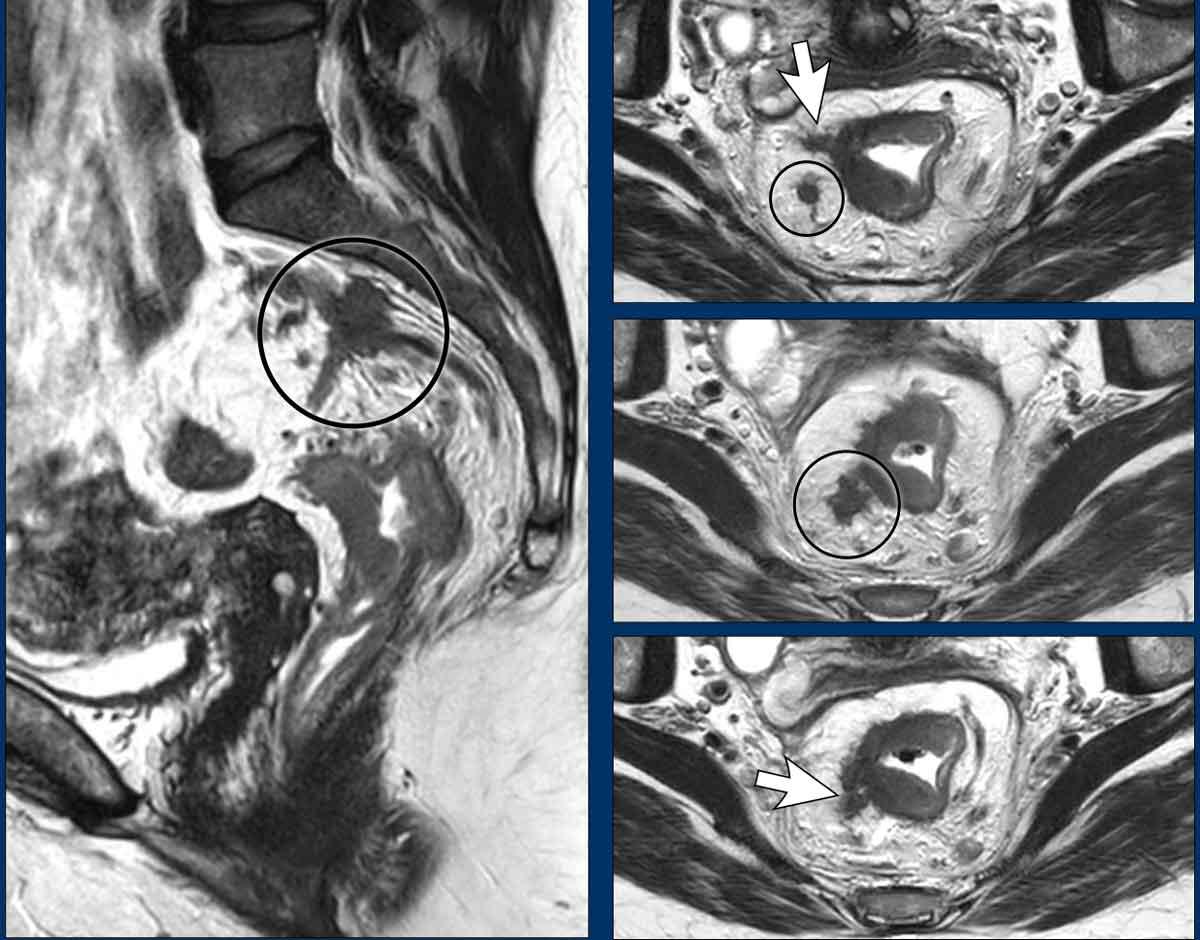

Khối lắng đọng khối u và xâm lấn mạch ngoài thành ruột (EMVI)

Các ổ di căn dạng nốt có mối liên quan chặt chẽ với EMVI, thường được coi là sự tiếp nối của quá trình lan rộng khối u theo đường mạch máu—bắt đầu với EMVI và tiến triển thành các ổ di căn dạng nốt trong giai đoạn bệnh tiến xa[ref].

Dữ liệu MRI cho thấy các ổ di căn khối u đồng xuất hiện với EMVI trong tới 80% trường hợp[ref].

Ví dụ Hình ảnh

- Mũi tên trắng: EMVI—tín hiệu khối u lan rộng vào các mạch máu lân cận, kèm theo sự giãn nở mạch máu và phá vỡ đường viền mạch máu.

- Vòng tròn đen: Các ổ di căn khối u được gieo rắc dọc theo các mạch máu.